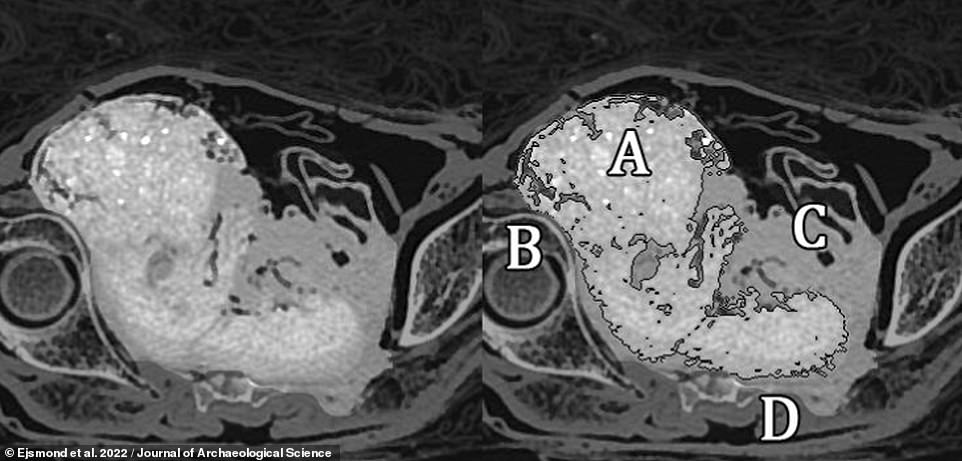

‘The foetus remained in the untouched uterus and began to, let’s say, “pickle”. It is not the most aesthetic comparison, but it conveys the idea!’ palaeopathologist Marzena Ożarek-Szilke of Poland’s University of Warsaw and her colleagues explained in a blog post. Pictured: two volumetric renderings of the foetus from the CT data. Labels on the right-hand image represent the head (A), right hand (B), left hand (C) and right leg (D)

A great deal of uncertainty surrounds the adult mummy specimen — dubbed the ‘Mysterious Lady’ — with experts presently unsure who she was and exactly what caused her death in her twenties back in the 1st century BCE. Pictured: a CT scan of the Mysterious Lady’s pelvic area. The foetus’ head is labelled as ‘A’, while its hand is labelled as ‘B’